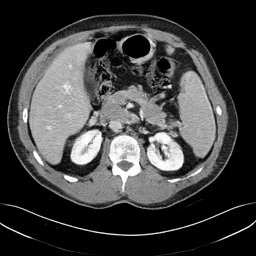

In many clinical settings, the use of both Computed Tomography (CT) and Magnetic Resonance (MRI) is necessary to pursue a thorough understanding of the patient's anatomy and to plan a suitable therapeutical strategy; this is often the case in MRI-based radiotherapy, where CT is always necessary to prepare the dose delivery, as it provides the essential information about the radiation absorption properties of the tissues. Sometimes, MRI is preferred to contour the target volumes. However, this approach is often not the most efficient, as it is more expensive, time-consuming and, most importantly, stressful for the patients. To overcome this issue, in this work, we analyse the capabilities of different configurations of Deep Learning models to generate synthetic CT scans from MRI, leveraging the power of Generative Adversarial Networks (GANs) and, in particular, the CycleGAN architecture, capable of working in an unsupervised manner and without paired images, which were not available. Several CycleGAN models were trained unsupervised to generate CT scans from different MRI modalities with and without contrast agents. To overcome the problem of not having a ground truth, distribution-based metrics were used to assess the model's performance quantitatively, together with a qualitative evaluation where physicians were asked to differentiate between real and synthetic images to understand how realistic the generated images were. The results show how, depending on the input modalities, the models can have very different performances; however, models with the best quantitative results, according to the distribution-based metrics used, can generate very difficult images to distinguish from the real ones, even for physicians, demonstrating the approach's potential.